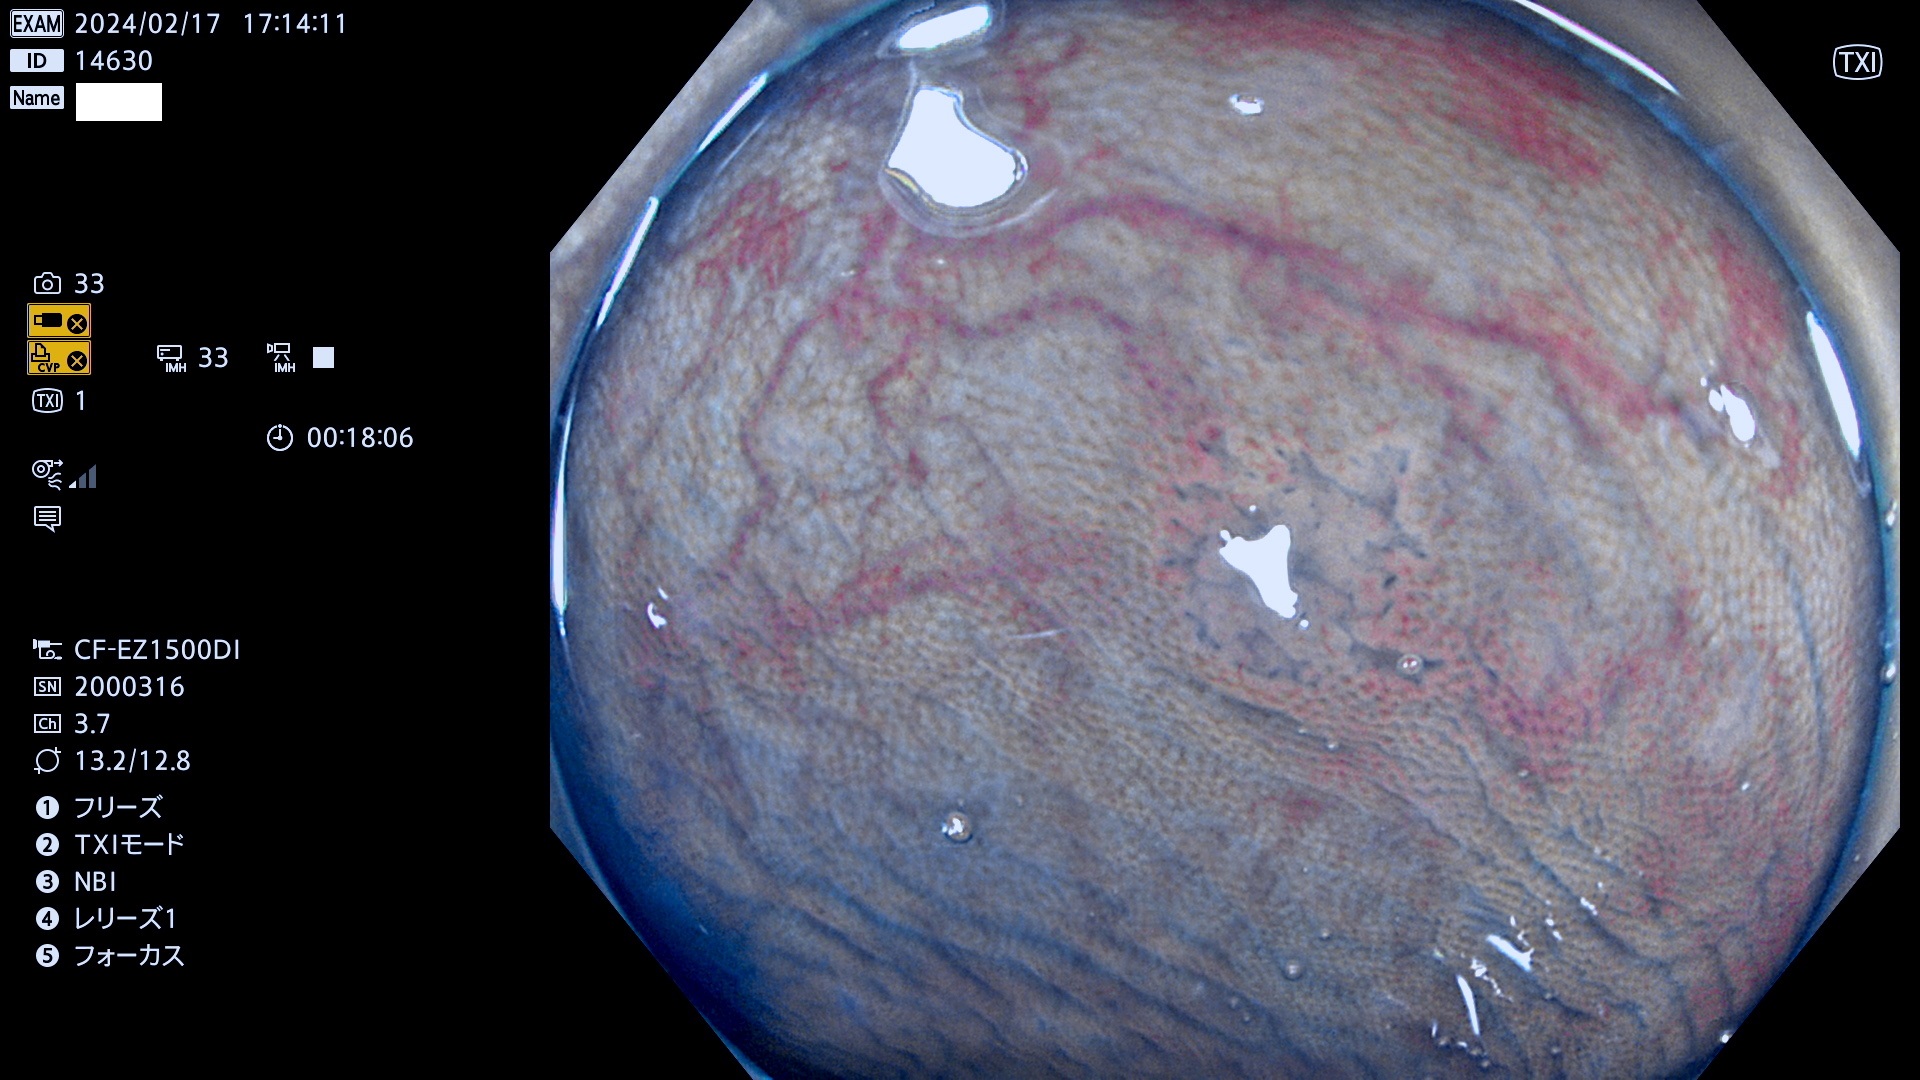

表面型腺腫(Flat Adenoma)の中で、完全に平坦な物をUb、陥凹している物をUcと呼びます。平坦隆起型(Ua)よりも、発見が難しく危険な病変です。

毎週の検査(木・金・土・日)に発見されたUb、Uc型・腺腫を、その週の日曜の夜にUPし1週間、提示します。

抽出の対象期間 2024年2月15日(木)〜2月18(日)の4日間(40件の検査)10件 (10/40=25%)